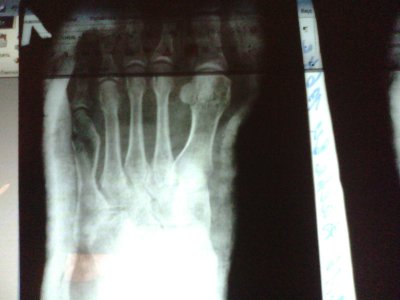

• IMG_20161224_170553.jpg

IMG_20161224_170553.jpg

223,3 КБ · Просмотры: 279